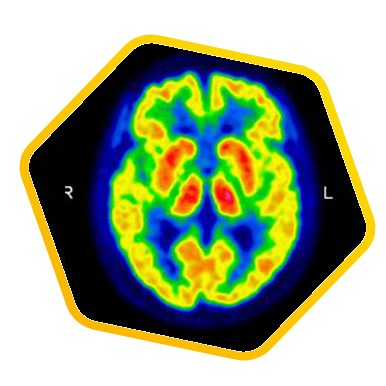

PET/CT scans with special tracers can show 3-dimensional images of blood flow and biomolecules deposition in the brain for diagnosis and monitoring the therapy progress of various neurological diseases, such as Alzheimer's, Dementia, Parkinson's disease, Huntingdon's chorea and autism. In 2018, the National Institute on Aging-Alzheimer's Association (NIA-AA) had revised the definition of Alzheimer's Disease (AD) from a syndrome diagnosed by a set of clinical criteria to a biological construct using abnormal protein deposits to define AD as a unique neurodegenerative disease that can lead to dementia. Our hospital has almost 20 years of experience in producing specific tracer to detect abnormal protein deposition in the brain.

- Epilepsy

For some types of epilepsy patients, PET/CT scans can localize the epilepsy-causing focus in the brain. Modern stereotaxic neurosurgery can then cure epilepsy permanently by excising the focus.